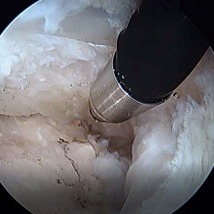

Minimally invasive surgery can be performed either through one small incision in the lateral hip or through 3-4 poke-hole incisions with the use of a camera and special instruments. The damaged trochanteric bursa is removed. The tendons are reattached to the lateral hip (greater trochanter) with suture anchors.